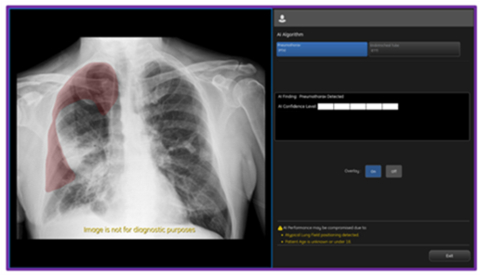

On-device, CCS2.1 output from GE HealthCare's AMX Navigate mobile X-ray system showing PTX overlay and confidence level. (Photo: GE HealthCare)

With this latest update, Critical Care Suite 2.1 provides immediate on-device detection and triage notifications for the presence or absence of pneumothorax (PTX). When a PTX is detected, an overlay is displayed in the area where the PTX was located both on-device as well as in PACS to assist with PTX localization, as well as improve speed and accuracy of PTX diagnosis. By hosting Critical Care Suite on-device, critical insights are available at the point of care and across the entire clinical care team.